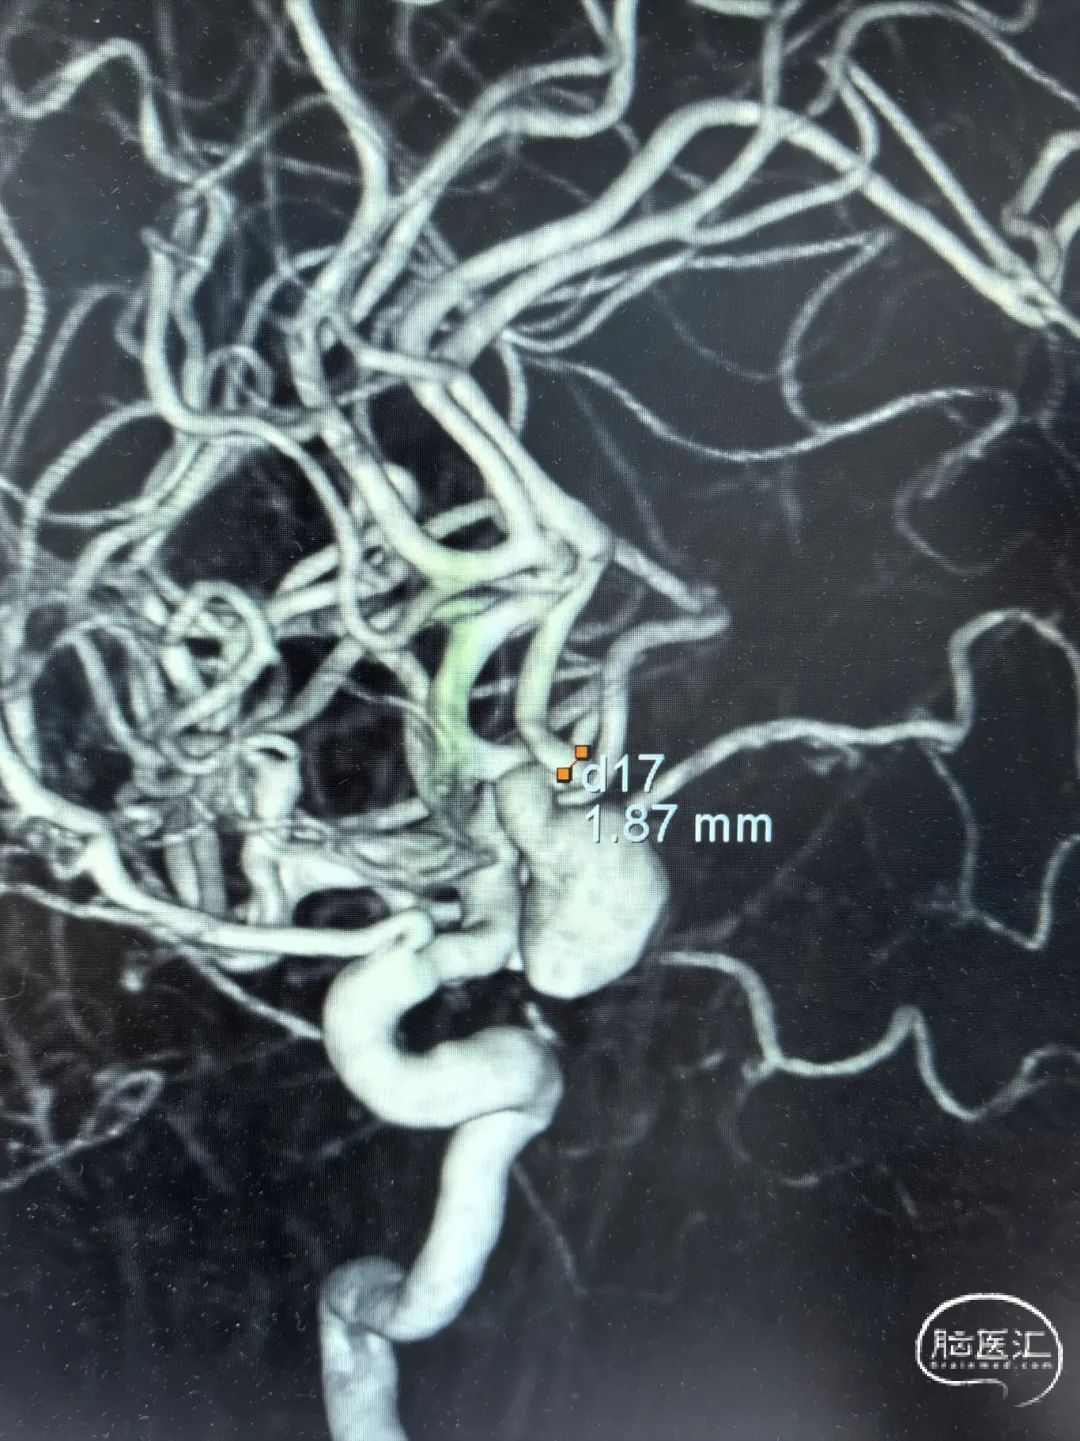

2025-1-19 DSA造影3D重建及方案讨论:

DSA造影3D重建测量

拟行脑动脉瘤密网支架置入术。

2.5mm*15mm Surpass Evolve密网支架,支架锚定区为右侧A2~A1